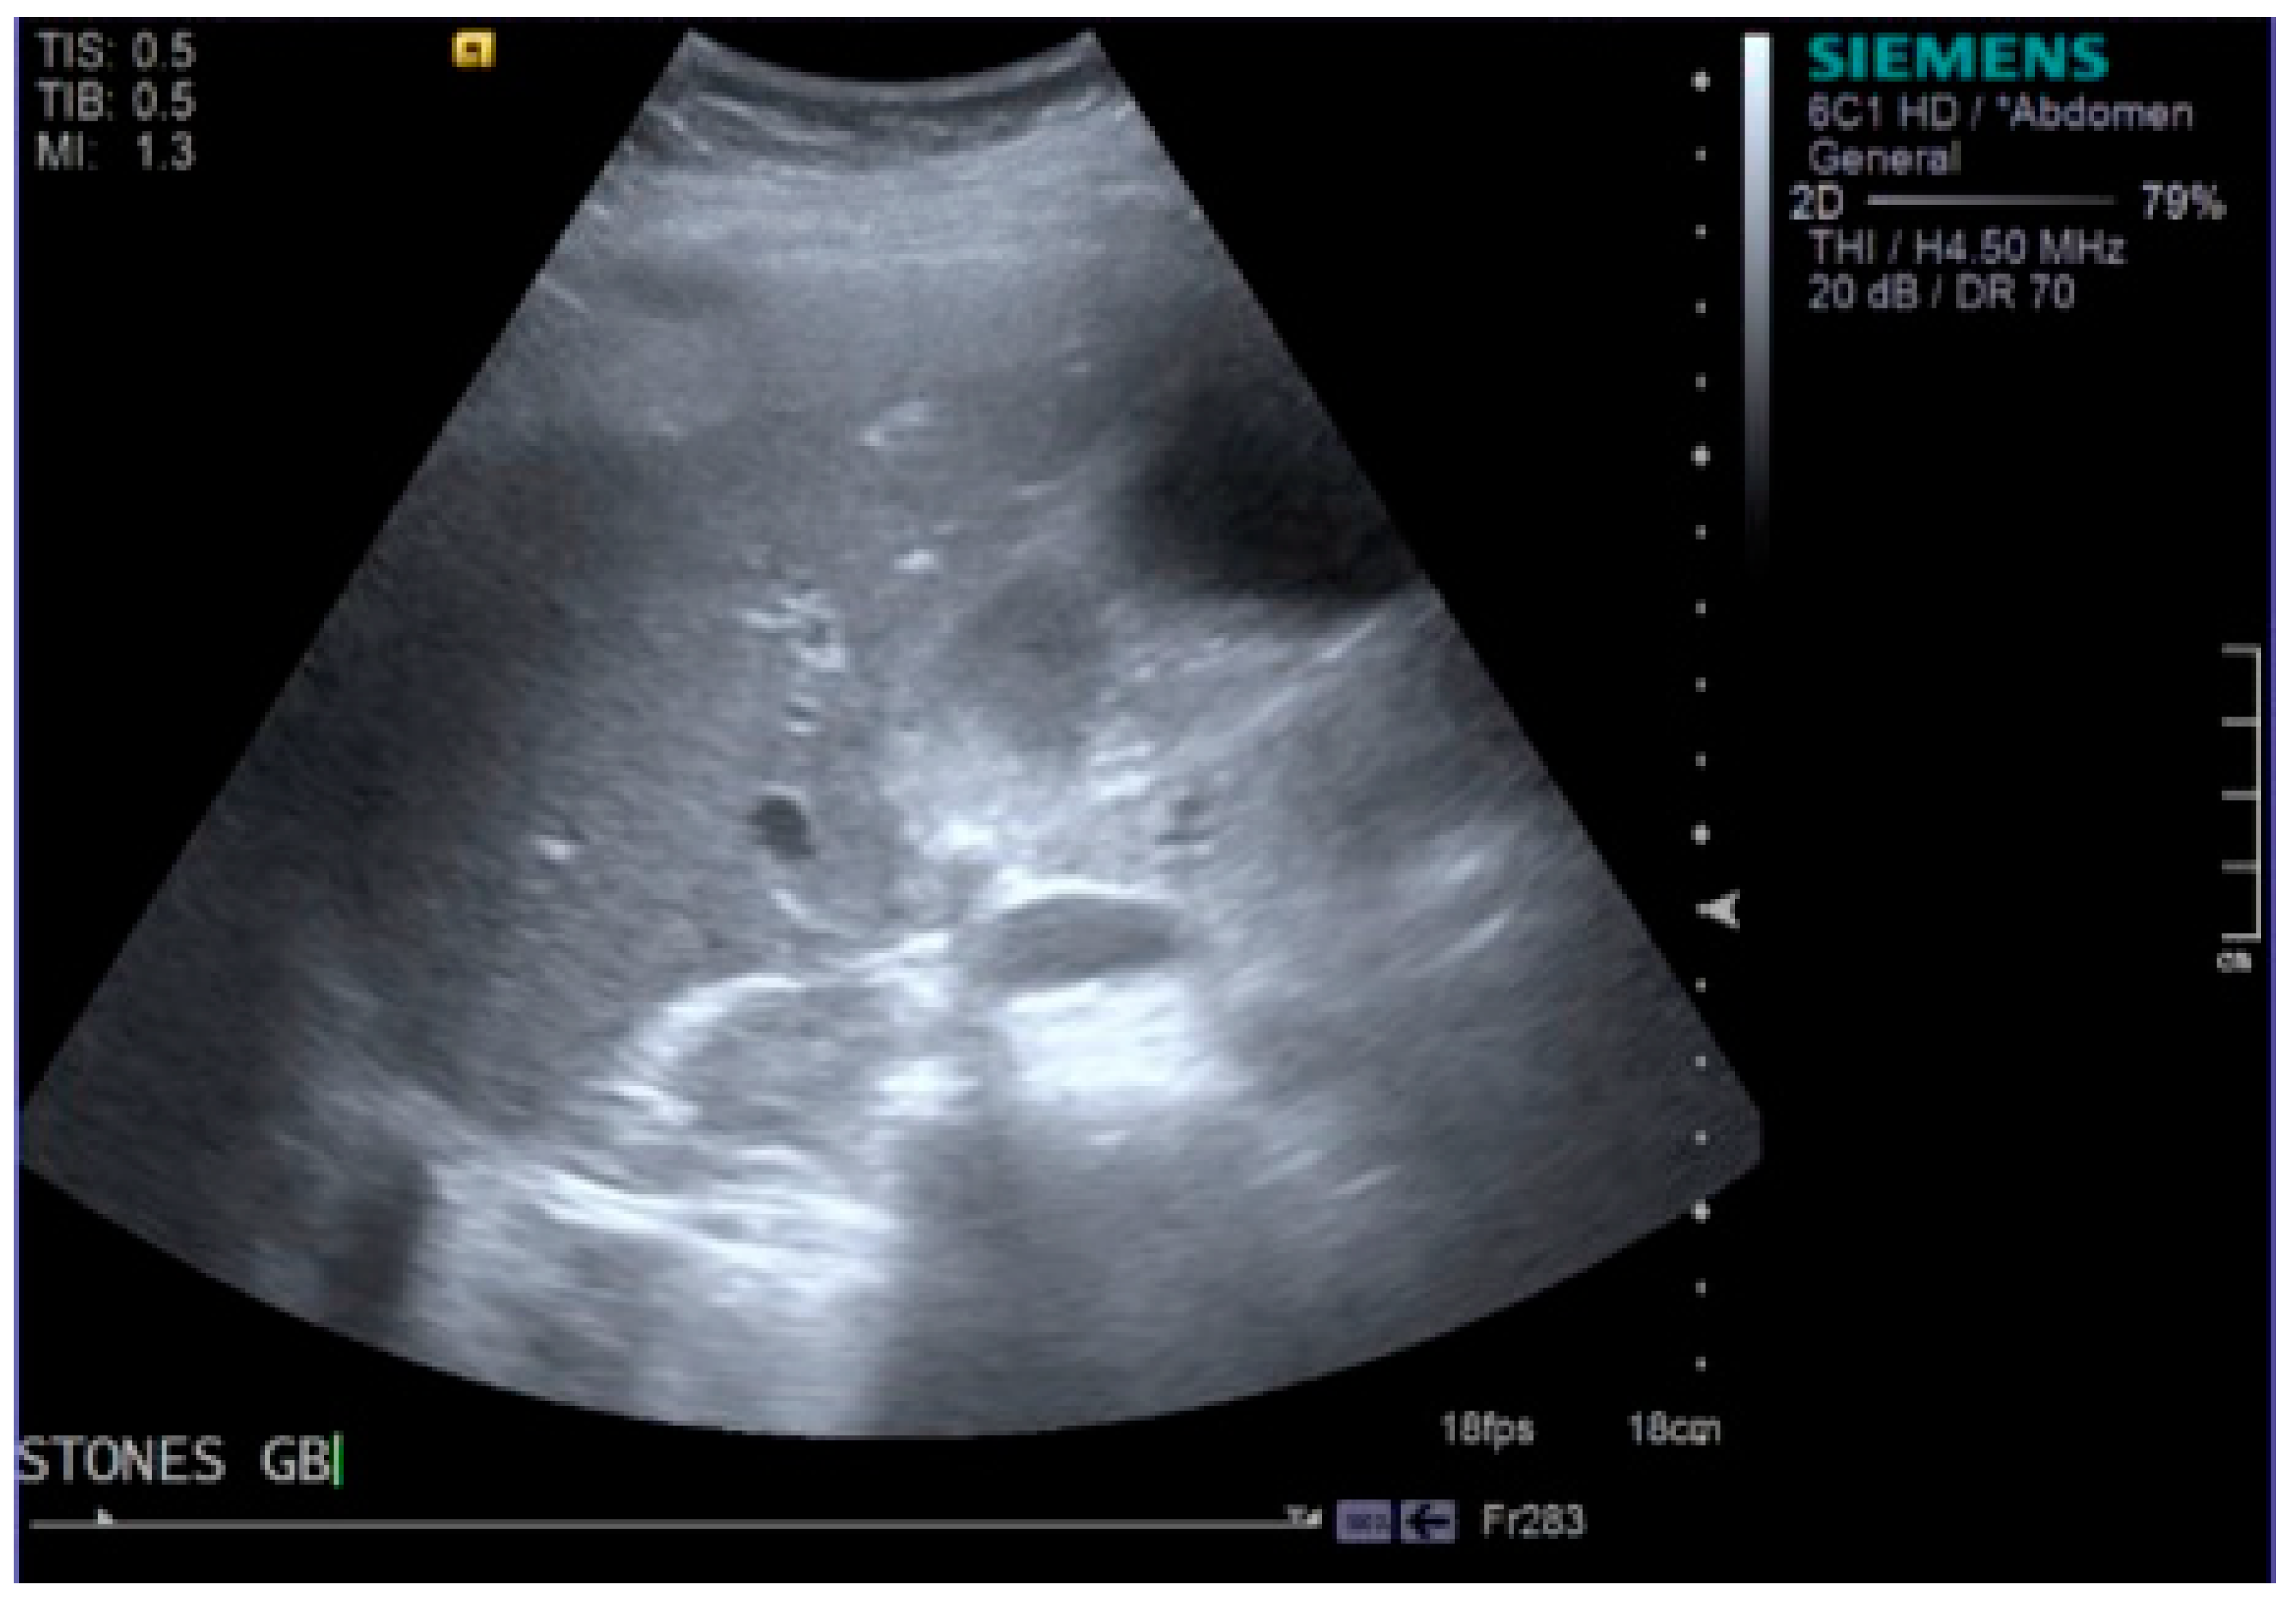

Intravenous access was obtained and blood tests taken. The patient was commenced on intravenous fluids, intravenous antibiotics and further analgesia before being admitted to the surgical triage unit. Initial blood results showed a haemoglobin (Hb) of 108 g/L, which was around the patient’s baseline. Bilirubin 185 µmol/L, alanine transaminase (ALT) 301 IU/L, alkaline phosphatase (ALP) 140 IU/L, amylase 3308 IU/L, c-reactive protein (CRP) 6 mg/L, white blood cells (WBC) 16.9 × 109/L and lactate dehydrogenase (LDH) 1085 IU/L. Urea and electrolytes, calcium and lactate were all normal. The blood results in addition to the clinical picture demonstrated an obstructive jaundice and acute pancreatitis, possibly secondary to gallstones. The patient scored a 2 on the Glasgow score [7]. Shortly following admission, the patient was requiring oxygen with an increase in all over body pain and further pyrexia. Observations were as follows; temperature 40 °C, heart rate 114 bpm, blood pressure 146/85, respiratory rate 22, saturating 100% on 4 L of oxygen. An ultrasound scan (USS) was obtained confirming acute pancreatitis with a dilated gallbladder containing dense debris and small calculi (Figure 1 and Figure 2). The common bile duct (CBD) measured 7 mm. Moderate pleural effusion on the right, small pleural effusion on the left. Repeat blood tests showed a Hb of 67 g/L, reticulocytes 3.4%, bilirubin 307 µmol/L, ALT 301 IU/L, ALP 121 IU/L, CRP 48 mg/L, WBC 9.7 × 109/L.

Figure 2.

Image taken from the ultrasound scan showing the presence of gallstones within the gallbladder.